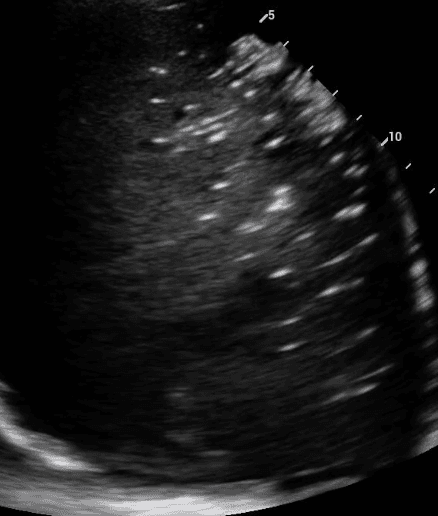

Consolidated lung appears dark due to its increased density and in some instances, may take on a similar texture to the liver. This is often referred to as “hepatization of the lung.”

Air bronchograms are air-filled bronchi that remain patent within the surrounding consolidated lung, They appear as hyperechoic structures within the hypoechoic consolidation. They may resemble multiple millimeter-long, lentil-shaped structures or branching tubular structures.

A shred sign represents the boundary between consolidated (abnormal) and aerated (normal) lung tissue. It appears as an irregular (shredded/fractal) line next to normal lung.